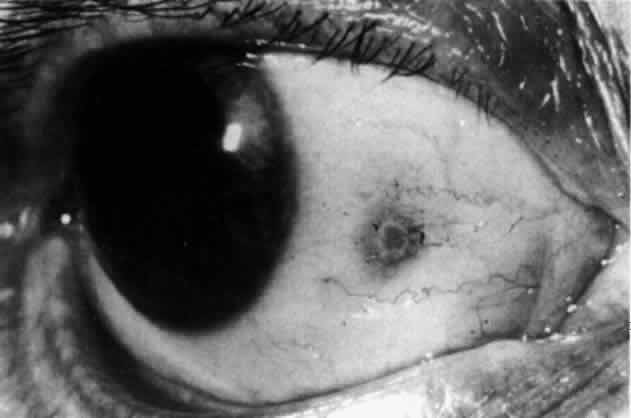

The object of slit lamp examination is to determine the depth and nature of scleral and episcleral conditions and the presence of corneal changes. The changes seen are drawn in the records. With the use of diffuse light with a neutral density filter, the vascular networks of both eyes are examined in detail to determine the layer in which the vessels show maximum congestion, the infiltration of episcleral tissues, and the edema of sclera, episclera, or subconjunctival space. Slit lamp examination is also used to ascertain the nature and depth of any corneal changes; the presence of scleral edema (for which it may be necessary to blanch the superficial tissues with epinephrine 1:1000 or phenylephrine 10%); the nature of any episcleral infiltration or mass; and the presence of cells in the anterior chamber or vitreous and posterior synechiae. The red-free (green) filter is extremely valuable in confirming the areas of maximum congestion and whether any areas are totally avascular. Because this is an important physical sign and is easily missed, examination in red-free light should be routinely performed. The green light brings the vessels into very sharp contrast with the background and enables the position of maximum inflammation to be determined with certainty. It also enables the paths and configurations of the vessels to be followed and will show lymphocytic infiltration of the episcleral tissue as yellow spots; this often indicates that the condition is more extensive than previously supposed (Fig. 8).

Fig. 8. Examination in red-free light. Blood vessels brought into sharp contrast reveal areas of lymphocytic infiltration in episcleral tissues, in this case due to herpes simplex virus.